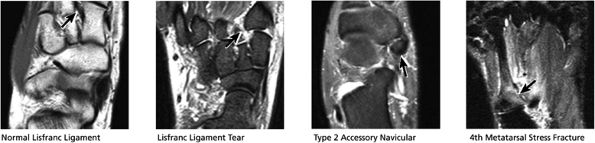

FIGURE 5.27 ● Axial anatomy of the ankle and foot. (A) The flexor digitorum longus, flexor hallucis longus, peroneus brevis, soleus, and extensor digitorum muscles are examined at this level for strain, tears, or fatty atrophy that may suggest denervation. (B) The tibialis anterior, extensor hallucis longus, and extensor digitorum longus tendons are examined on every ankle MR examination. Extensor tendon pathology is frequently overlooked if these tendons are not included as part of the ankle checklist. (C) Tears and sprains of the anterior syndesmotic ligament are a frequent cause of persistent ankle pain following ankle sprain. The syndesmotic ligaments are thick, tough ligaments that are important ankle stabilizers, and delayed diagnosis of syndesmotic tears may result in significant degenerative arthrosis at the tibiotalar joint due to the resulting ankle instability. The syndesmotic ligaments course obliquely inferiorly from the tibia to the fibula and are not usually visualized in their entirety on a single axial image; rather, their course is followed on at least two or three successive axial images. (D) The peripheral margin of the peroneal tendons and tibialis posterior tendon should normally never extend beyond the peripheral margins of the lateral and medial malleoli, respectively. Tendon subluxation around the posterior corner of either malleolus is indicative of a tear of the overlying flexor retinaculum (medially) or peroneal retinaculum (laterally). When the retinacula are torn, the tendon is free to intermittently sublux or dislocate, leading to tendon degeneration, pain, and tendon dysfunction. (E) Suspected osteochondral lesions of the talar dome are visualized and further characterized on axial images through the top of the talar dome. (F) The peroneus brevis tendon may normally appear somewhat flattened. However, as the tendon degenerates, it becomes U-shaped and drapes around the anterior aspect of the peroneus longus and becomes impinged between the peroneus longus tendon and the lateral malleolus. With further degeneration, the peroneus brevis may split or completely rupture. (G) Evidence of anterior talofibular ligament injury is visualized on the majority of MR ankle examinations and appears as thickening, intermediate signal with ill-defined fibers, or attenuation of the ligament. This is commonly asymptomatic. (H) Because the flexor hallucis longus tendon sheath communicates with the tibiotalar joint, fluid may normally be present within the tendon sheath in proportion to the amount of fluid in the tibiotalar joint. If there is fluid within the tendon sheath out of proportion to that seen in the tibiotalar joint, tenosynovitis is most likely present. The finding of flexor hallucis longus tenosynovitis should prompt a search for an os trigonum, as impingement of the flexor hallucis longus tendon between an os trigonum and the posterior tibial plafond is a common cause for FHL tenosynovitis. (I) The calcaneofibular ligament (CFL) passes anterior and medial to the peroneal tendons. On the image at which the CFL passes directly medial to the peroneus brevis tendon, the appearance of the peroneus brevis and the CFL side by side is occasionally mistaken for a split peroneus brevis tendon. (J) Dilated posterior tibial veins within the tarsal tunnel occasionally compresses the tibial nerve. In the setting of clinical suspicion for tarsal tunnel syndrome or if there is evidence of muscle denervation on MR images, the size of the posterior tibial veins should be described. (K) The spring ligament is identified at this axial image location, extending from the anteromedial calcaneus to the posteromedial navicular. Tears of the spring ligament may result in medial instability and hindfoot valgus. (L) The posterior tibialis tendon (PTT) may normally become thickened and fan-like as it passes posterior to its navicular insertion (prior to also inserting on the cuneiforms and the base of the second through fourth metatarsals). In the absence of other findings, the thickening of the PTT at this level should not be mistaken for focal tendinosis. (M) On inferior images through the ankle, Lisfranc's ligament is occasionally included in the FOV. Lisfranc's ligament extends from the medial cuneiform to the base of the second metatarsal. If Lisfranc's ligament is included in the FOV, the status of the ligament should be described, as undiagnosed Lisfranc ligament tears can lead to debilitating midfoot arthrosis. (N) As the medial and lateral tendons turn from their vertical course to a horizontal course along the plantar aspect of the foot, the tendons may demonstrate a magic-angle artifact, causing the tendons to appear gray on short-TE images, mimicking tendinosis. Correlation with images using longer TE values is advised in such situations.

The spring ligament complex consists of three components: the lateral, intermediate, and superomedial oblique calcaneonavicular ligaments.